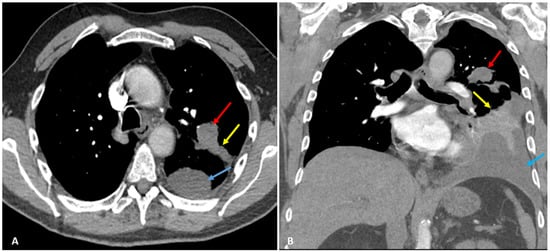

2. Case Presentation